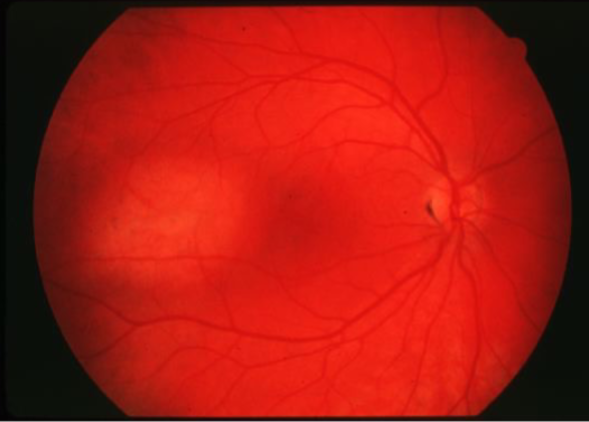

solitary choroidal hemangioma

choroidal hemangioma

choroidal hemangioma

choroidal hemangioma

choroidal hemangioma

choroidal hemangioma